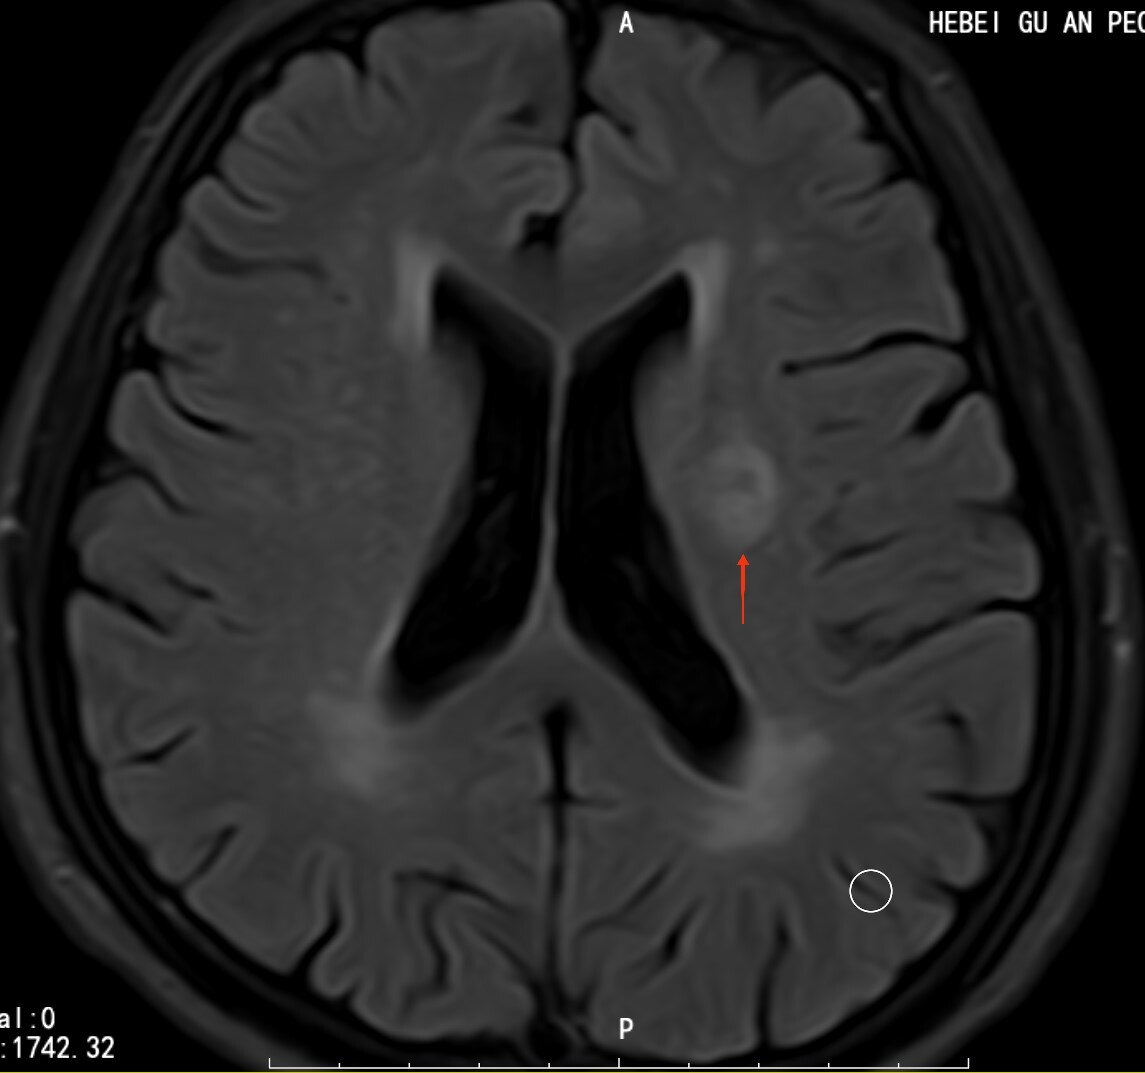

症状与影响软化灶本身通常不直接引发症状,但其位置和大小可能影响周围脑组织功能例如,若软化灶位于运动皮层,可能导致肢体无力或协调障碍若在语言中枢,可能引发言语不清若在感觉区域,可能出现麻木或疼痛此外,软化灶可能增加癫痫发作风险,尤其是当病变累及皮质时检查方法磁共振成像MRI是。

辅助检查根据需要开展脑电图EEG脑血管造影血液检查等,排除其他病变密切观察与随访定期复查MRI等,监测软化灶变化针对病因治疗若软化灶由感染血管病变等可治疗因素引起,需进行相应干预康复治疗对出现神经系统症状的患者,通过康复训练恢复功能注意事项脑软化灶的处理需个体化决策。

若软化灶较小,可能无任何临床表现若较大或位于运动区语言区等重要功能区,则可能引发以下神经系统症状1运动障碍如肢体无力瘫痪共济失调等2感觉异常如麻木疼痛感觉减退3言语障碍包括失语构音障碍语言理解困难4吞咽困难如饮水呛咳吞咽困难5认知障碍如记忆力下降注意力不集中。